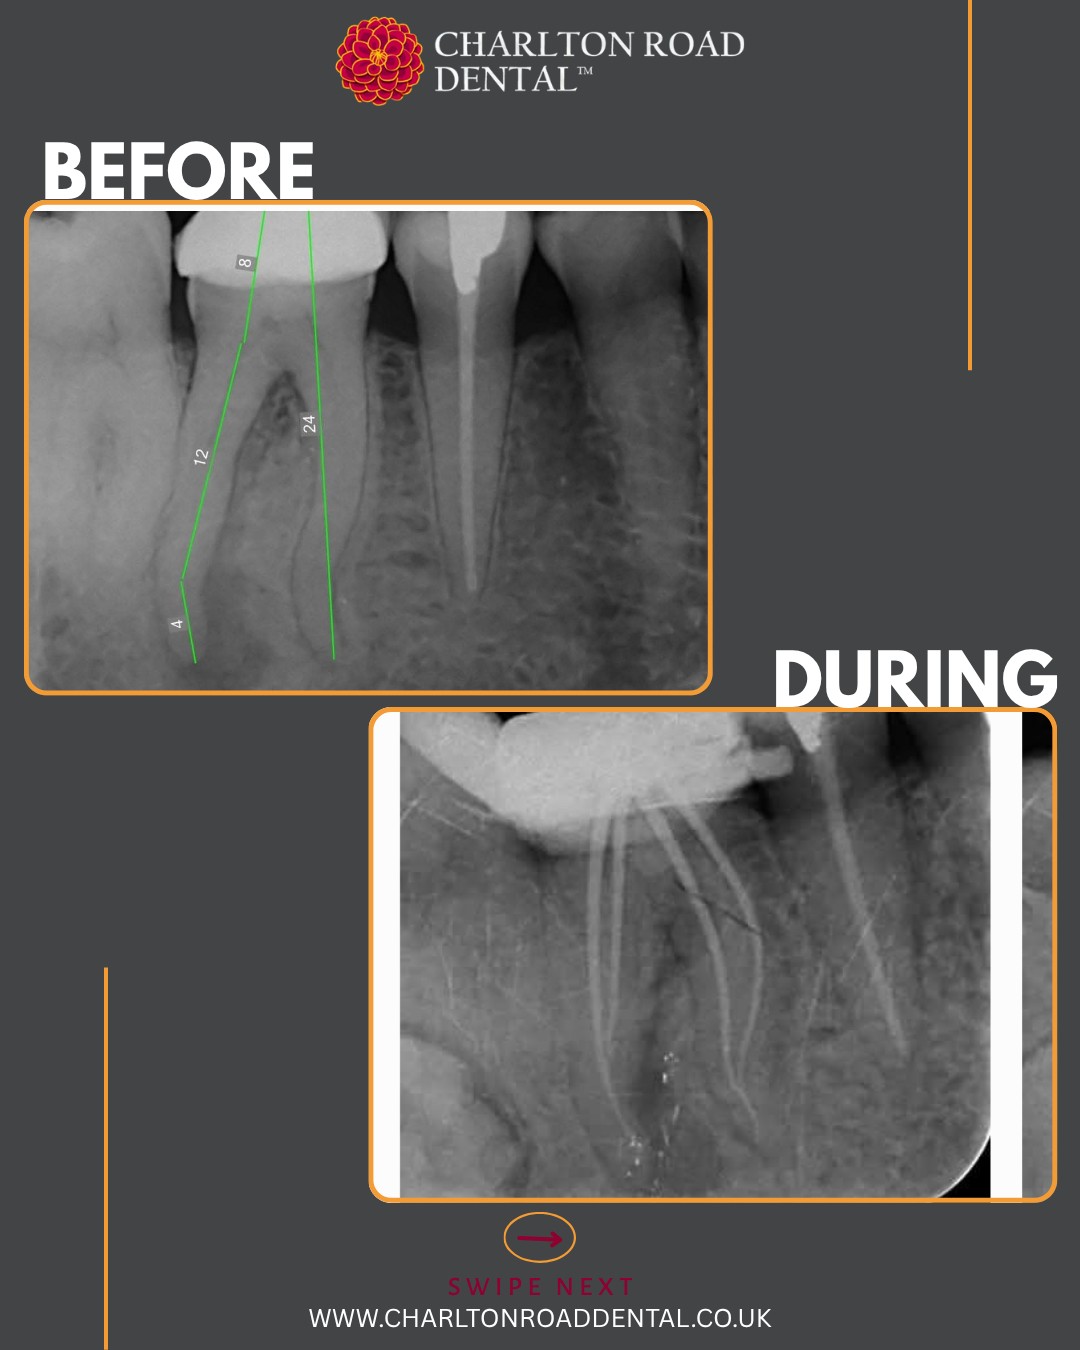

S-shaped curves in molar canals are ideal for putting the VS Flexi Blue files to the test. These files offer excellent flexibility and allow for conservative shaping of the canals, thereby preserving precious tooth structure.

First up: a UL6. Periodontal treatment has been completed and stabilised. This was a necrotic case with a history of an acute flare-up a few months ago. I used the existing filling as a reference to help orient the access cavity. Numerous pulp stones were encountered.

I prepared the DB and palatal roots first, allowing the MB root to soak in disinfection solution in the meantime. I instrumented the MB root system up to size 20/06, and up to 25/06 in the palatal and DB roots. Irrigation was performed using full-strength sodium hypochlorite and Endo solution, delivered with Irriflex tips. I used a yellow EndoActivator for agitation and micro-suction to dry the canals.